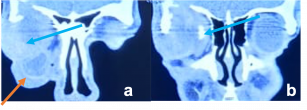

| Thyroid Eye Disease[16] | Young adults; Female > Male | Axial Proptosis, Redness, watering, lateral flare, lid retraction, photophobia.

Restrictive myopathy |

CT- spindle enlargement of EOMs occurs with relative normal tendinous insertion (coca-cola bottle sign).

MRI - Bulky EOMs are isointense on T1, slightly hyperintense on T2W images and show enhancement. |

Most frequent involvement IR>MR>SR>LR. Superior Ophthalmic Vein may be enlarged due to apical compression | Axial and coronal section of non-contrast CT images of orbit showing three different patterns of TED. a) Bilateral fusiform enlargement of the extraocular muscles sparing the tendinous insertion with posterior crowding (orange stars) b) Bilateral fusiform enlargement of the extraocular muscles sparing the tendinous insertion along with increased orbital fat. c) Bilateral increased orbital fat (denoted by increase of hypodense areas of fat attenuation). EOM appears normal. |